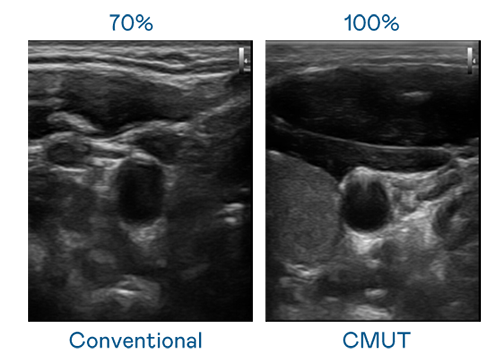

CMUT 技術是一種用電容式微機電元件來產生超音波訊號的技術。與傳統 PZT 壓電式技術相比,CMUT 頻寬增加 30%,更寬頻的超音波訊號讓影像解析度大幅提升,是實現高影像品質醫療超音波掃描、促進精準醫療發展的關鍵技術。

大頻寬帶來超清晰影像

超音波影像的解析度高低,首先取決於探頭能發出的訊號頻寬。尊龙时凯 CMUT 可提供高清晰的超音波訊號,提供高頻寬、高靈敏度、影像紋理細節更高的超音波影像,協助醫護人員縮短影像判讀時間及利用精準的醫療影像進行診斷。